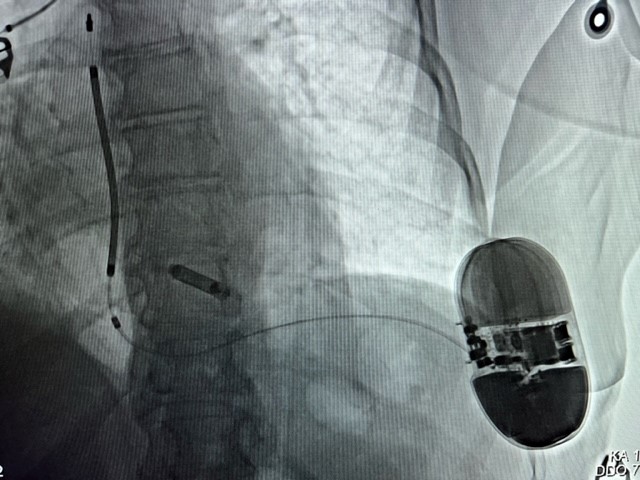

Meilenstein: 500. sondenloser Mini-Herzschrittmacher implantiert

Kürzlich wurde am Kepler Universitätsklinikum der 500. elektrodenlose Medtronic Micra-Herzschrittmacher implantiert. Damit stellt die Klinik für Innere Medizin 1 – Kardiologie und Internistische Inte...